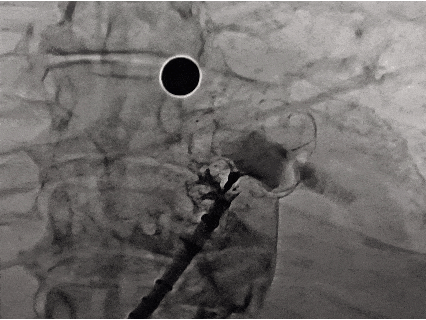

Seal 密封

代表密封,即观察封堵器密封情况,封堵完全,残余分流不超过5mm

肝位即刻造影,位置合适

上下缘无残余漏,形态位置良好

右肩位造影,无残余漏

封堵完全

正足位造影,上下缘无残余漏